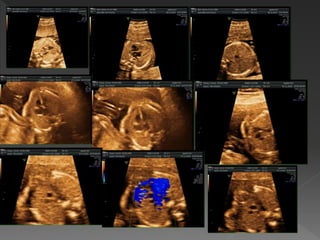

 Dört odacıkkesitinde görülen ek anormallikler:  Ventriküler septal defekt  Kardiyak tümörler  Total anormal venöz drenaj  Sol atriyal izomerizm İlk örnek, septumun girişinde büyük bir VSD gösterir (iki AV kapakların arasında uzanan septum). İkinci örnek, apikal muskuler VSD gösterir (Renkli doppler olmadan zor görülür). Kalp döngüsü sırasında çift yönlü akım defektten geçer (mavi ve kırmızı). Tüm VSD Ventriküler Septal Defekt

 Dört odacıkkesitinde görülen ek anormallikler:  Ventriküler septal defekt  Kardiyak tümörler  Total anormal venöz drenaj  Sol atriyal izomerizm Rabdomyom. Multipl rabdomyomlar %95 oranında tüberküloz ile ilişkilidir. Kranyal MR sıklıkla intraserebral tümörleri gösterir. Rabdomyom

 Dört odacıkkesitinde görülen ek anormallikler:  Ventriküler septal defekt  Kardiyak tümörler  Total anormal venöz drenaj  Sol atriyal izomerizm Pulmoner venlerin normal pozisyonda sol atriyuma arkadan bağlandığı görülmez. Normal sol atriyum şeklini ve sol atriyum-inen aorta arasındaki artan mesafeye Total Venöz drenaj anomalisi